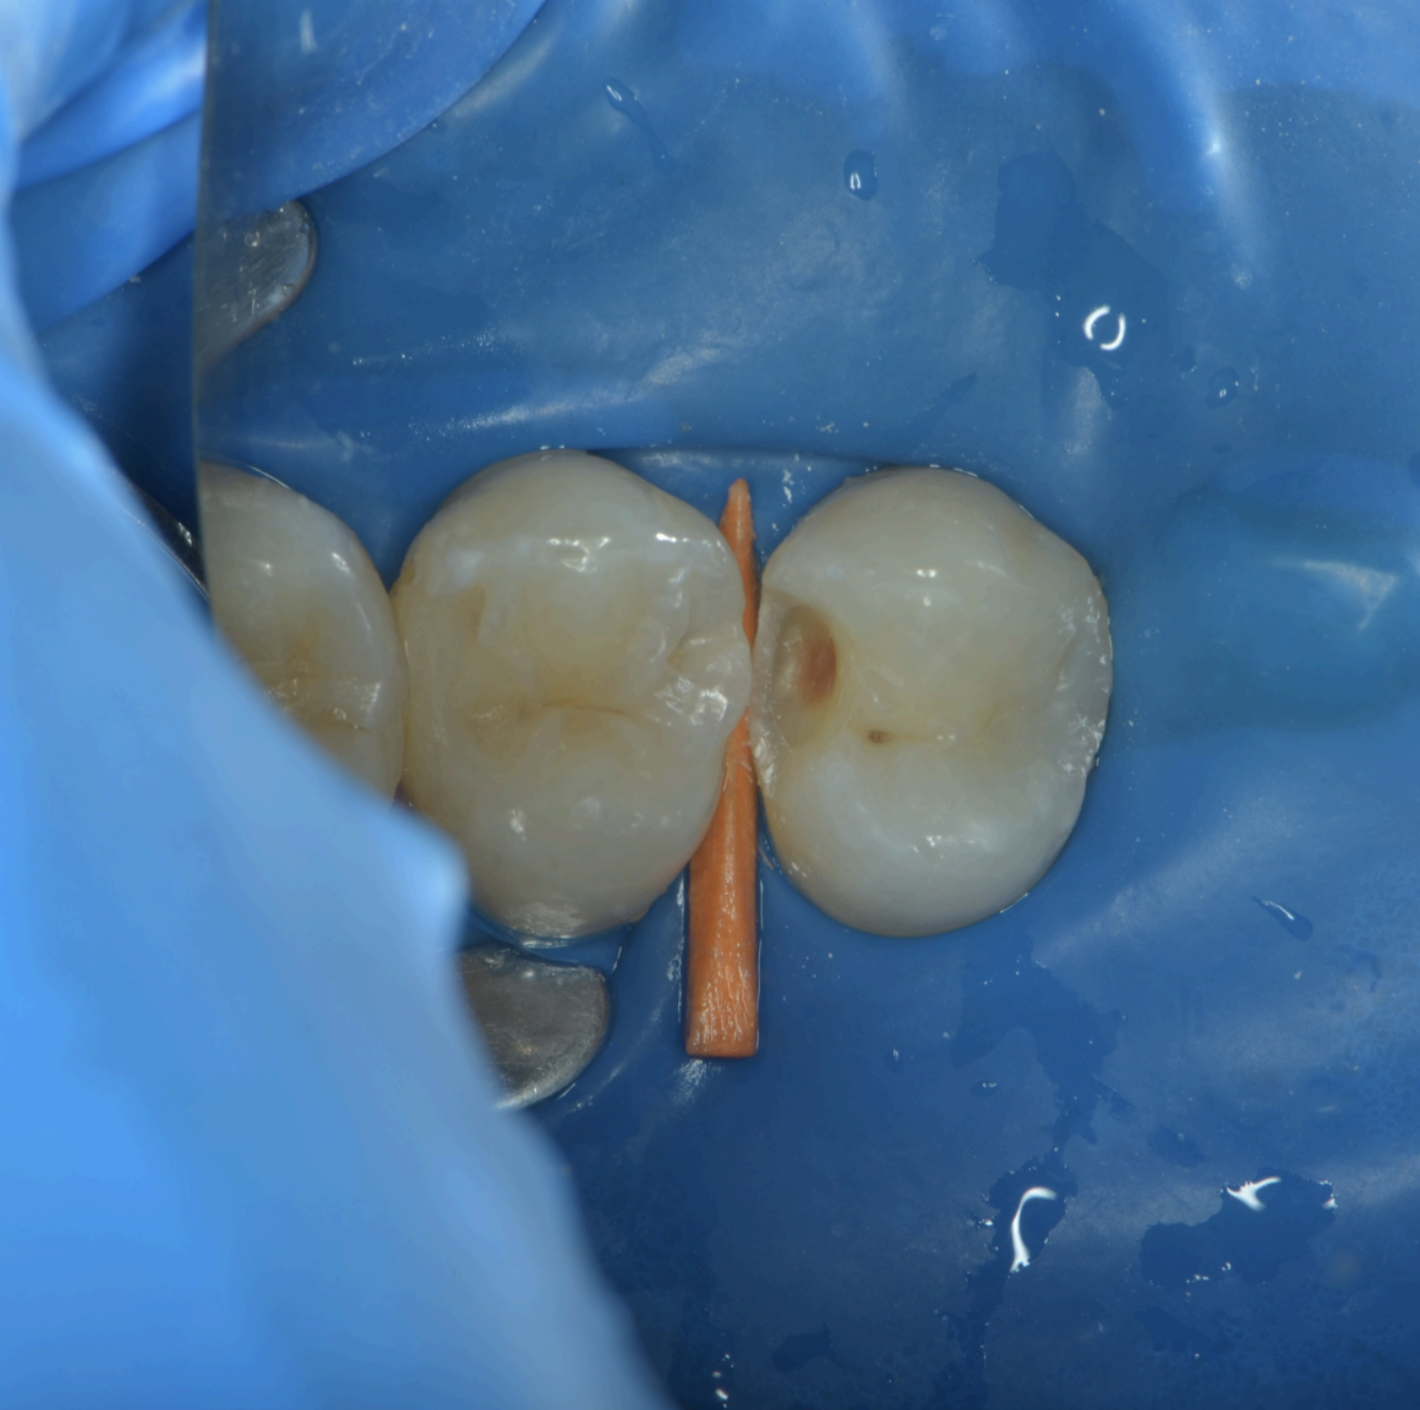

Dupa ce leziunea carioasa a fost indepartata si am ajuns la tesuturile dentare dure si sanatoase (Fig 3), se trece la restaurarea peretilor pe care i-am indepartat la pasul anterior. Pentru aceasta eptapa, avem nevoie de un suport de metal pe care se va construi peretele din material compozit – acest suport de metal poarta denumirea de “matrice” si ea poate fi de mai multe feluri. Matricea se aplica intre dinti pentru a reface peretele, iar ea este fixata in loc printr-un “ic” de lemn, sau “pana” care o va mentine apasata de smaltul dentar restant- oferind o sigilare optima si impiedicand aparitia locurilor goale la interfata dinte-restaurare.